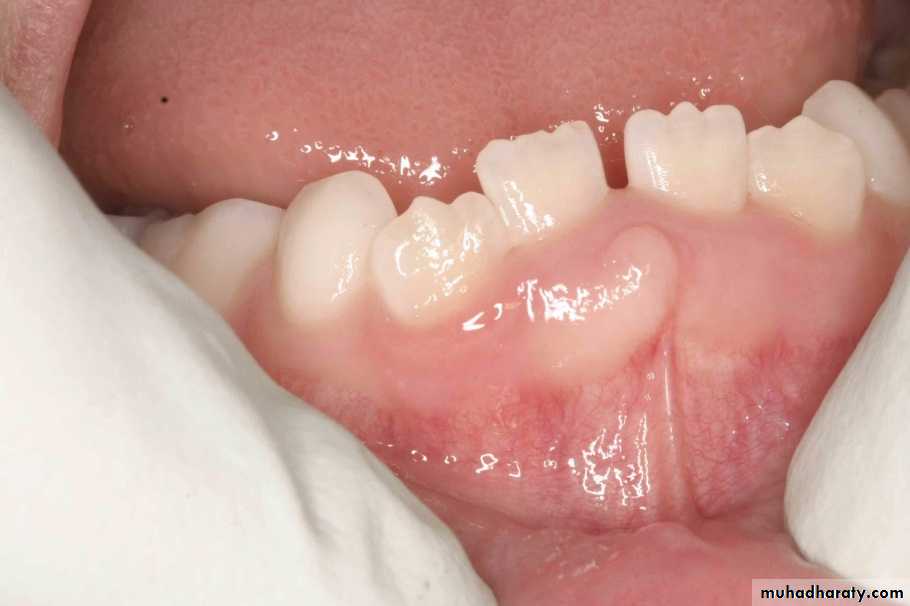

pyogenic granuloma

• Is a benign, elevated, and capillary-rich lesionIs, soft, red or purple mass on the lips, interdental papilla, or buccal mucosa .• It may occur in the skin.

• The cause is thought to be local irritation, hormonal factor or trauma.

• When located at the gingiva of pregnant women, the term pregnancy tumor may be used.

• An oral pyogenic granuloma most frequently involves the gingiva.

• The lower lip and the dorsal surface of the tongue are rather common sites as well.• The lesion is usually pedunculated or sessile, and the surface is often ulcerated.

• The size of the lesion's diameter may vary from 0.5 to 2 cm or more.

• Sometimes rising the question of whether one is dealing primarily with a vascular lesion with secondary signs of inflammation or with an inflammatory condition.

• Mitotic activity may be abundant and should not be mistaken as a sign of malignancy.

• Surgery is the management of choice. Recurrence rare.